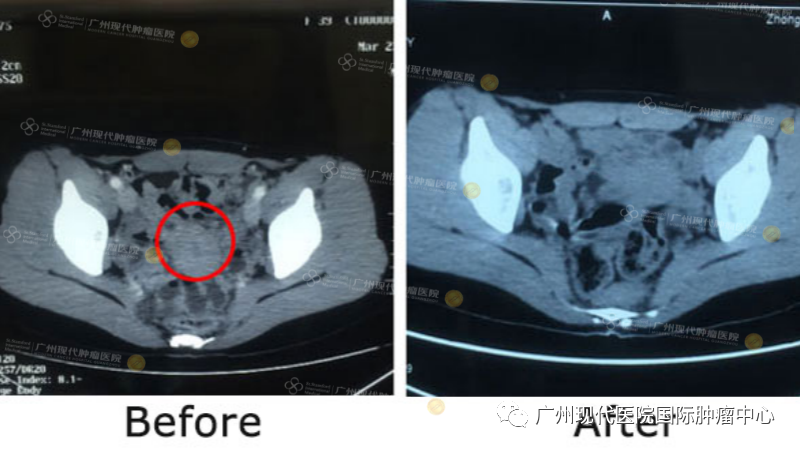

生活中难免有挫折 2016年10月在一次偶然的体检中,我确诊为宫颈癌IB期。我平时热爱运动,且作息规律,却“中奖”了,于是对突如其来的噩耗毫无心理准备,心里不安且害怕,但我依旧相信总会有办法的。 当地医生建议我立刻进行手术以防病情恶化,但我当时已经报名参加了古巴的马拉松,决定比赛结束后再做打算。比赛结束后我在新加坡的一家医院再次进行检查,医生给的建议是化疗,考虑到化疗的副作用会影响我的生活质量,让我成为终日卧床的病人。我拒绝了医生的建议,回到印尼,继续寻找更好的治疗方法。 2016年,我在布拉格参加马拉松 一切都是最好的安排 我是一名互联网技术工作者,我相信世界上拥有全新癌症靶向治疗技术,便一直在谷歌搜索。不幸中的万幸是,我在网上看到了圣丹福广州圣丹福肿瘤医院,靶向性的微创治疗让我眼前一亮,仿佛抓住了救命的稻草。 2016年12月,我满怀希望来到这里。但病情的发展却出乎意料,宫颈癌已经恶化到IV期(肿瘤大小约6.2cm x 3.7cm)蔓延直肠、肝脏和膀胱,我非常震惊。MDT团队为我制定了治疗方案:介入治疗+自然疗法并增强了免疫。 一次疗程之后,我感觉自己身体和心态慢慢变好。在治疗过程中,我经常到医院不远处的白云山爬行,从艰难的一步步,直到能够到达山顶甚至其他山顶。我对治疗过程和效果很满意,我本认为最困难的是过程,可是这里的医生和护士很友好,耐心地倾听我,真诚地关心和帮助我,深深地打动我。 微创治疗前后检查结果对比 告别癌症 2017年6月,我像以往一样回到医院进行复查。再次见到医护人员、翻译员,他们都为我活泼的状态而感到开心。医生告诉我一个好消息,CT检查结果显示癌细胞活性几乎“消失”,各项指标都已接近正常。令我更惊喜的是,医护人员准备了生日蛋糕和美食来为我庆祝生日。他们环绕着我唱生日快乐歌的那一刻,我感到自己既幸运又幸福。 医护人员为我庆祝生日 这才是真正的我... 我是一名主厨 以前我不会做饭,因工作繁忙,无瑕好好享受生活,生病之后我慢慢意识到健康的重要性。在住院期间,我经常会自己在院内厨房烹饪健康的食物。2017年5月,在家休养期间我在巴厘岛参加了一个烹饪班,向一位日本厨师学习烹饪技巧,并取得证书。一同参加烹饪班的同学感到无法置信,我竟曾经患有宫颈癌IV期,所有人都为我如今的健康表示祝贺。 我和巴厘岛烹饪班的同学 我的烹饪证书 我是一名潜水员 我热爱大自然,经常跟朋友一起旅游、登山、潜水、健身,去感受所有美好的一切。这次患上癌症就像生命中的一次历险,而我的人生在这次经历中也得到了升华。感谢圣丹福广州圣丹福肿瘤医院给予我重生的机会,让我以后能够继续精彩生活、享受生活。 2011年,我和朋友徒步登上龙目岛林加尼火山 2012年,我在印尼巴布亚省的极乐岛湾潜水,与大白鲨合照 2016年,我在拉布汉巴焦的科莫多岛 我是马拉松运动员 2018年3月,这是我告别癌症之后,再次享受我最大的爱好。我在喜马拉雅山跑马拉松,完成了42公里的成就。这个过程非常艰难,因为喜马拉雅山海拔非常高,所以经历缺氧。当时在我脑海里闪现的是,一副副癌症患者的面孔。我想把每一公里都献给他们,希望他们同我一样勇敢抗癌,然后获得成功和健康。我就这样一公里接着一公里坚持,直到42公里。 2018年3月,我在喜马拉雅山跑马拉松 我是癌症幸存者 2023年10月,我出席了圣丹福广州圣丹福肿瘤医院雅加达办事处举办的癌症幸存者见面会,时隔8年,如今我以癌症幸存者身份分享抗癌经历,我感到开心。癌症教会了我更加明确活着的意义,我希望能够尽自己的努力,把机会和祝福带给别人,希望他们也能获得良好的治疗,从而健康和幸福。 2023年10月,我参与雅加达办事处癌症幸存者见面会 我是抗癌明星 2023年11月,我再次来到圣丹福广州圣丹福肿瘤医院。此次前来,首先为了参与“漫漫抗癌路,暖暖现代情”抗癌明星志愿者回基地活动。使我满怀期待的是,能够再次见到曾经照顾我的医护人员,有机会再次感谢他们给予的细心照顾以及给予我的第二个生命。 在癌症治疗中,我特别感谢丽丽护士对我极大的帮助,耐心也好,鼓励也好,是我最困难时候的一束光,让我感动不已。感恩之情道不尽,所以我把自己认为目前最大的成就——喜马拉雅山马拉松42公里的奖牌赠送于她,才能表达我深切感激之情。 我把喜马拉雅山马拉松奖牌赠与护士 我是作家、慈善人员 上帝经圣丹福广州圣丹福肿瘤医院的医护人员把福气带给我,让我重获健康的身体。我想把这份福气继续传播下去,所以我写了一本书,分享我生活中所遇到的挑战和经历,希望把积极的心态传染给别人。在疫情期间,我也不断做慈善工作,尽我所能帮助正在面临困难的人们。所以,我希望幸福能够从我手中一直不断循环。 我战胜癌症之后写的一本书 “我一直坚信,我们每个人身体里面都住着一个更大的自己。面临癌症,或者其他困难,只要敢于挑战,就能战胜我们所想战胜的。希望正在面临癌症以及任何困难的朋友们,永不放弃,勇于挑战!” 我鼓励其他患者的话 微创技术介绍 介入治疗 介入治疗,在医学影像设备引导下穿刺,利用特制导丝等精密器械,将比静脉点滴药物浓度高2~8倍的抗肿瘤药物直接注入肿瘤内部,同时对肿瘤的供血动脉进行栓塞,实现肿瘤缩小甚至消失的目的。 1. 具备创伤小、并发症少、安全、恢复快的优势。 2. 适合采用传统放化疗效果不佳、不愿或不适合做手术等情况的患者。